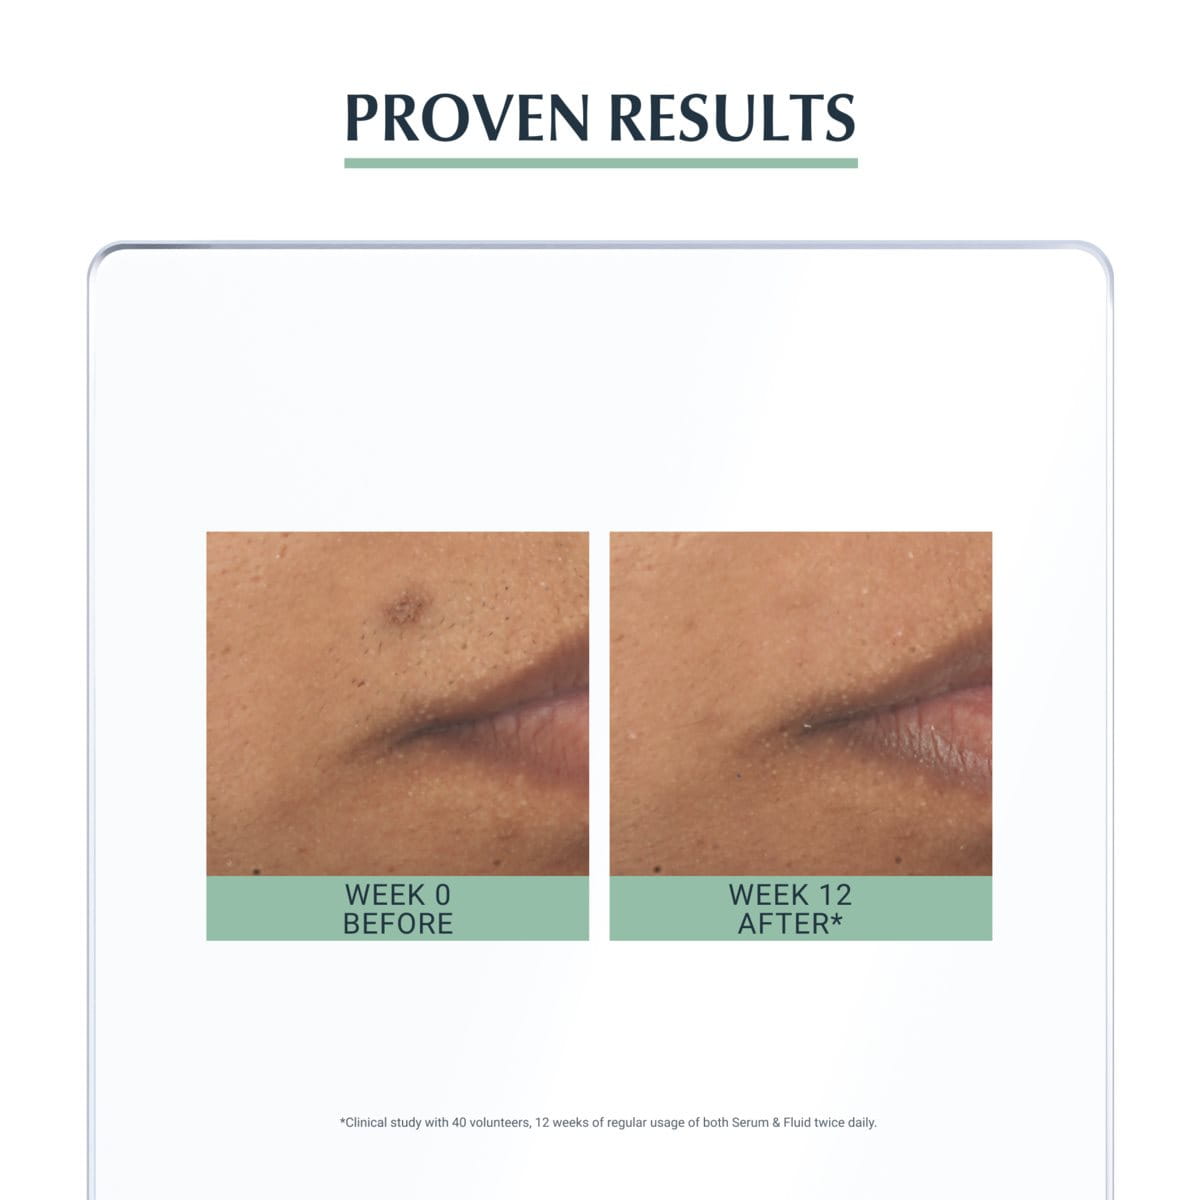

Clinical and dermatological studies

Good skin tolerability and efficacy on blemish-prone skin with post-blemish marks. Clinically proven to visibly reduce post-blemish marks by up to 80% (1) and blemishes by up to 90% (2). Visibly improves pores by up to 71% (2). First visible results in 2 weeks. (1) Clinical study with 40 volunteers, 12 weeks of regular usage of Serum twice daily. (2) Usage of Serum & Fluid twice daily. Among other clinical and dermatological studies, a Product in Use (PIU) study was conducted, with 100 volunteers over 8 weeks of regular use twice a day*. They reported the following results after 8 weeks of regular use: